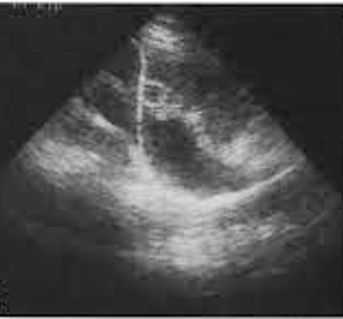

- Nefrostomia direita com punção guida por USG

- Duplo J anterógrado Esquerda